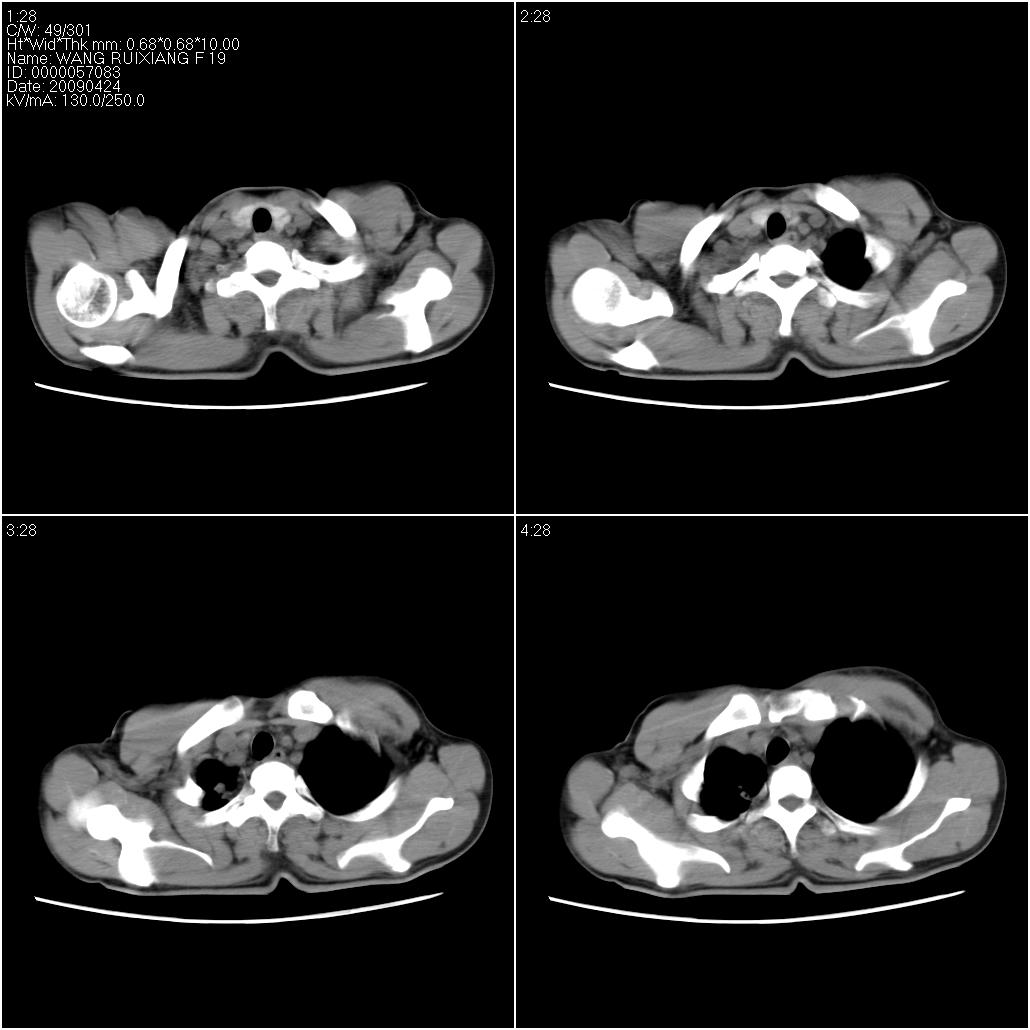

片子上的年龄为19岁,是操作错误。该患者于去年5月份曾做平片和ct扫描,和这一次的ct检查没有明显变化。当时诊断为肺结核,进行抗痨治疗至今,但没有改善。呼吸功能试验为混合型呼吸困难。除此之外,该患者没有其他方面没有的临床症状和体征

考虑肺淋巴管腺肌病,其次考虑间质性肺炎\\肺间质纤维化及韦格氏肉芽肿等

结合病人年龄(特别是生育期妇女)及临床表现多考虑淋巴管肌瘤病。